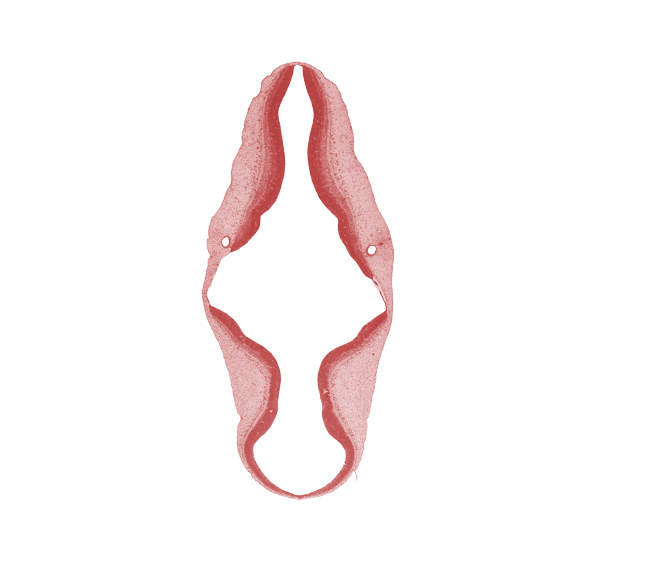

Keywords: alar plate(s), artifact separation(s), basal plate, cephalic edge of vestibular part of otic vesicle, endolymphatic duct, isthmus of rhombencephalon, mesencoel (cerebral aqueduct), rhombencoel (fourth ventricle), roof plate, sulcus limitans, vascular plexus

Source: The Virtual Human Embryo.